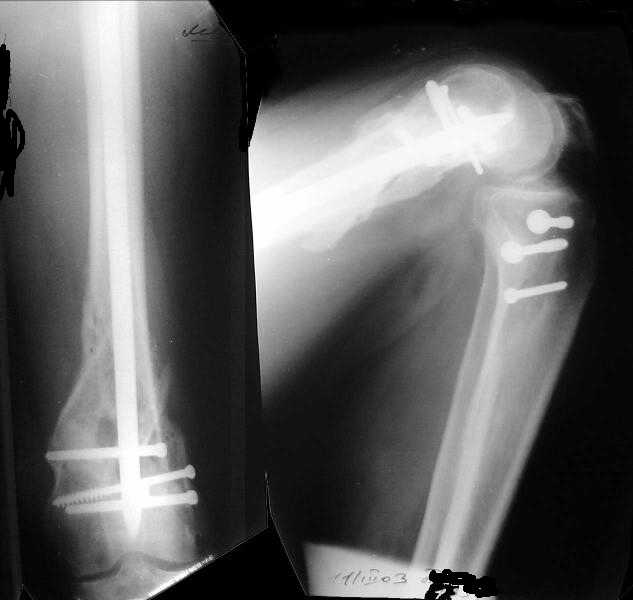

1

Sorry but I've just prepared postop images - attached. A solid 13 mm nail was used. A few degrees of recurvation appears to be which i missed on image intensifier. I'm still uncertain about

advantages/disadvantages of ante/retrograde nailing for such fractures.

The fixation as you have done is excellent. The locking screws on either side of the # are so apart. When we put in a supracondylar nail thro a keyhole incison in the knee, the locking bolts will be nearer the # and will be more stable allowing him to bear wt early. That was the reason the supracondylar nail was innovated. The locking is done by jig and no freehand method saving time.